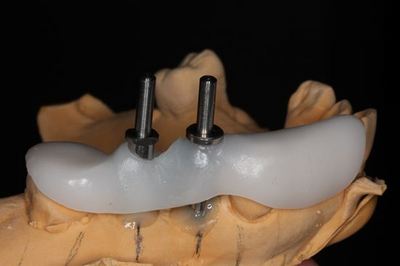

いつものように埋入計画を立て、サージカルステントの作製をします。